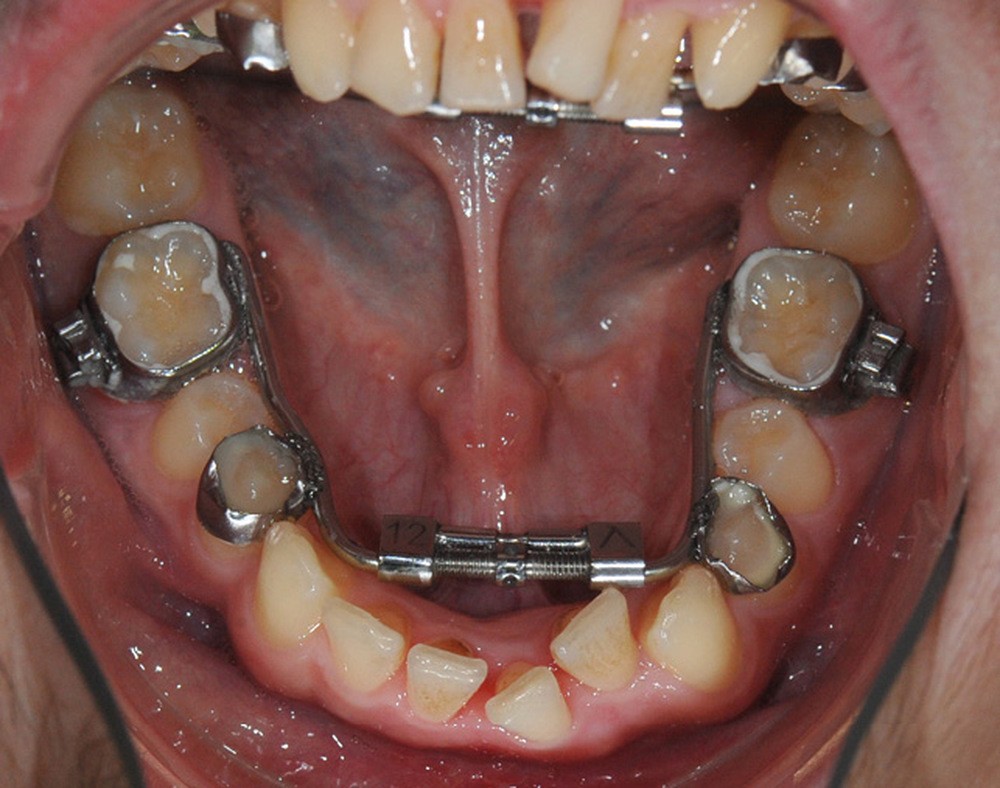

Le Dr Paul Cresseaux présentera dans un premier temps un ancrage squelettique, simple et efficace, développé par ses soins, pour optimiser la préparation orthodontique des classes II squelettiques : l’Abalakov (fig. 13a-d). Puis, il défendra la prise en charge simultanée, au cours d’un unique temps chirurgical, de l’ensemble des anomalies squelettiques présentées par nos patients.